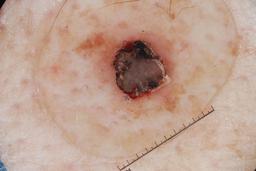

MSK-4

- Name: MSK-4

Description:

Images found based on a search for patients with a personal history, clinical diagnosis, or differential diagnosis of melanoma. All diagnoses confirmed by histopathology.